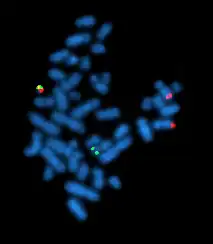

Fluorescence in situ hybridization

Fluorescence in situ hybridization (FISH) refers to using fluorescently labeled probe to hybridize to cytogenetic cell preparations.

The slide is aged using a salt solution usually consisting of 2X SSC (salt, sodium citrate). The slides are then dehydrated in ethanol, and the probe mixture is added. The sample DNA and the probe DNA are then co-denatured using a heated plate and allowed to re-anneal for at least 4 hours. The slides are then washed to remove the excess unbound probe, and counterstained with 4',6-Diamidino-2-phenylindole (DAPI) or propidium iodide.

Analysis

Analysis of FISH specimens is done by fluorescence microscopy by a clinical laboratory specialist in cytogenetics. For oncology, generally, a large number of interphase cells are scored in order to rule out low-level residual disease, generally between 200 and 1,000 cells are counted and scored. For congenital problems usually 20 metaphase cells are scored.